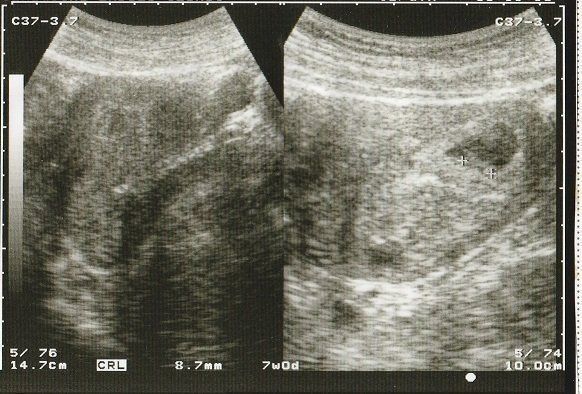

妊娠7週目のエコー写真 徐々に大きくなっていく胎芽

妊娠の喜びととともに不安も大きかった日々。毎週病院で検査してもらい、徐々に成長している過程を確認して、ホッと胸をなで下ろしていました。

妊娠8週目のエコー写真 10mm以上に成長

CRL(頭殿長=頭からおしりまでの長さ)が10mmを超えました。

順調に大きくなっていますが、まだまだ「大丈夫だろうか?」という不安が大きかった時期。